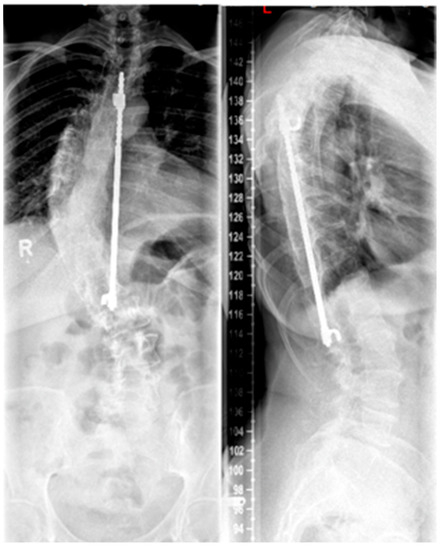

Figure 4. (a,b). Preoperative representation of the scoliosis and (c,d). Postoperative image following expansion thoracoplasty and implantation of the vertical expandable prosthetic titanium rib (VEPTR), attached proximal to the rib and distal to the laminae (reprinted with permission [10]).

3.5.2. Vertical Expandable Prosthetic Titanium Rib

The VEPTR system is a special type of scoliosis correction, and it is not considered as a classic growing rod. Originally, the system was used in children with congenital and highly progressive spinal deformities including unilateral brace formation and rib deformities with impending thoracic insufficiency syndrome [44]. The average age of 3.3 years at the time of surgery is lower for the VEPTR procedure in contrast to the TGR procedures. Currently, the main indication is thoracic scoliosis in congenital scoliosis with rib fusion, unilateral unsegmented braces, and contralateral hemivertebrae. This deformity is associated with severe thoracic asymmetry and markedly limited vital capacity of the lungs. The advantage of expansion thoracoplasty is that secondary correction of the spine can be achieved via correction of the rib deformity by rib osteotomies and VEPTR implantation without using a second approach in this area and thus increasing the risk for spontaneous fusions [45]. The VEPTR is a longitudinal, extendable titanium implant that is anchored to each of the caudal and cranial ribs using hooks of the concave hemithorax; see Figure 4. This “titanium rib” is also surgically expanded approximately every six months until growth is complete. Components may have to be replaced when the distraction distance is depleted. The main complication is cut-out or dislocation of the fixation to the ribs. By modifying the implant design, the complication rate could be reduced. In addition to intercostal connections from rib to rib, the VEPTR also offers the possibility of fixation to the laminae of the vertebral bodies or support on the pelvis.